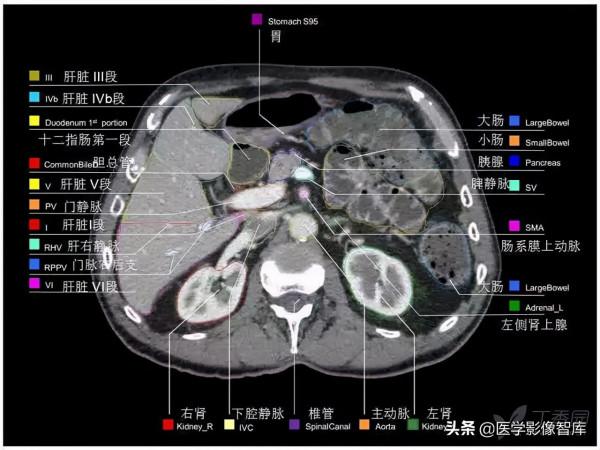

腹部CT